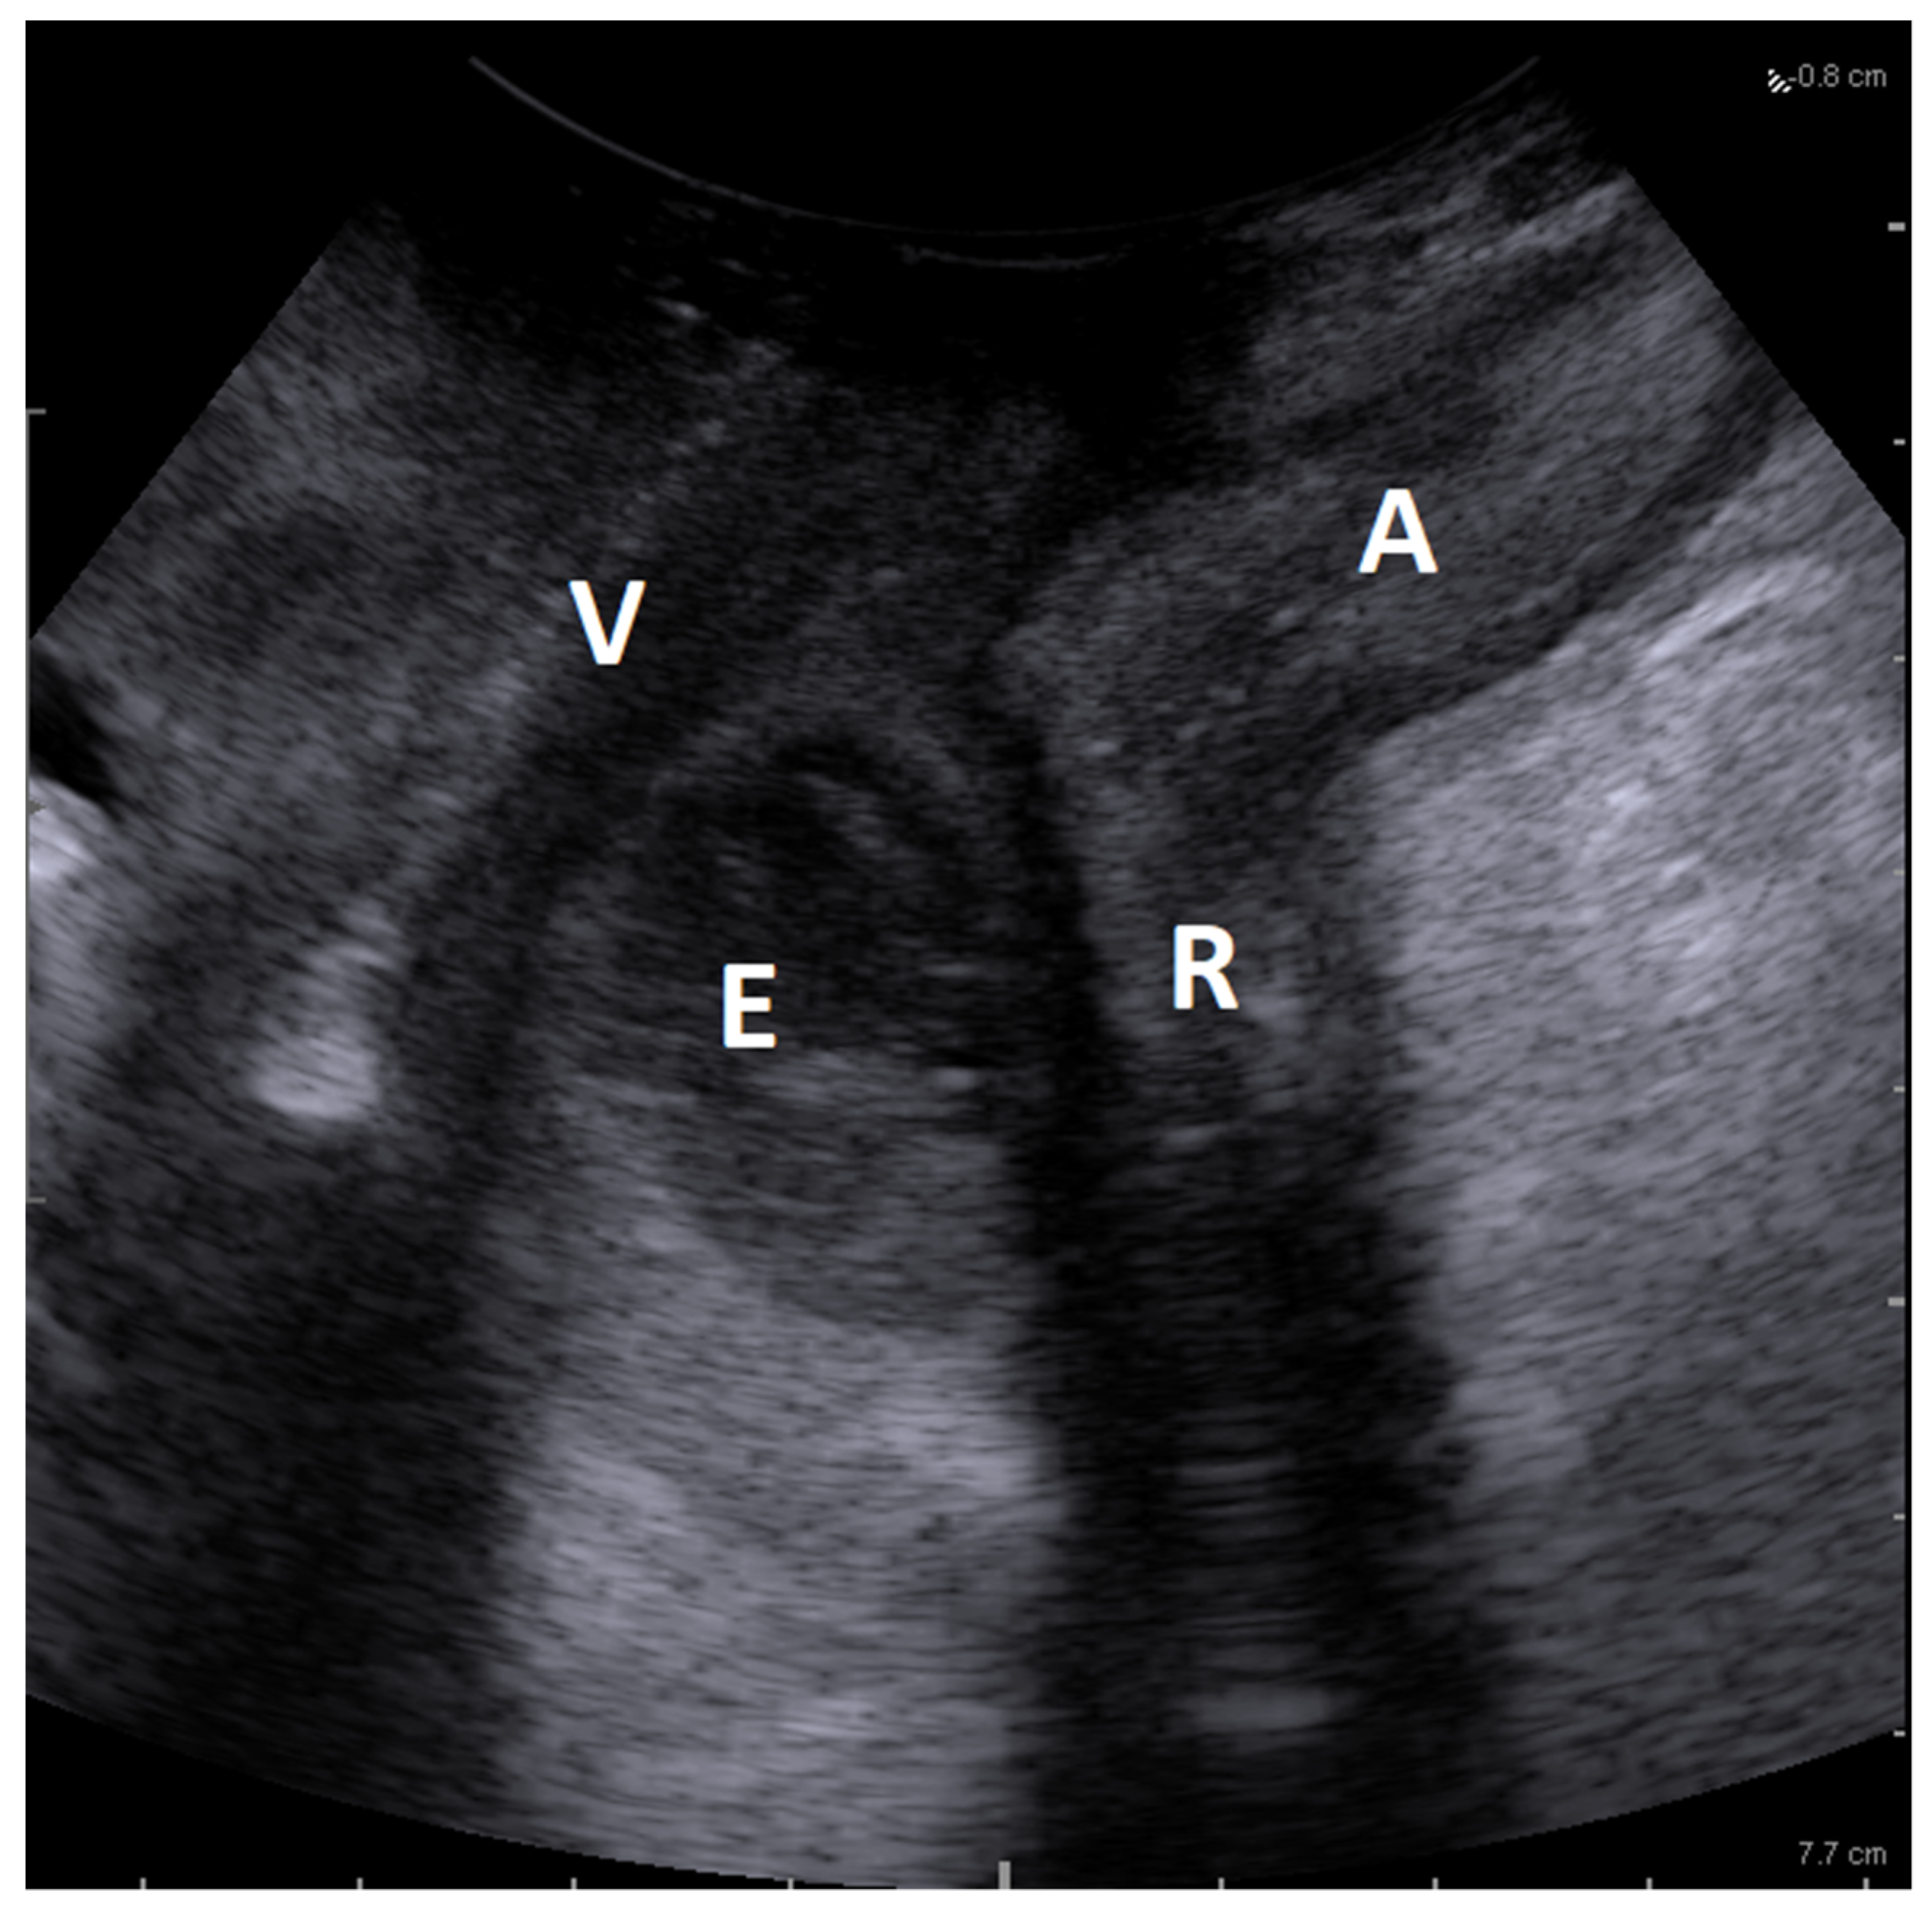

4.3. Imaging